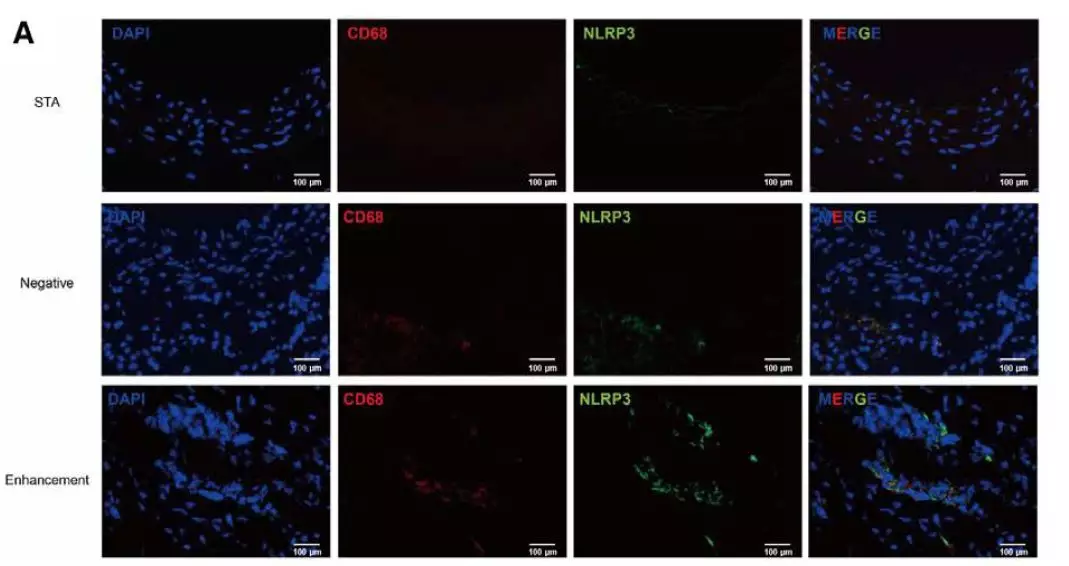

通过瘤壁标本病理检测结果与术前HRVWI强化信号分型对比: CD68和NLRP3在强化的动脉瘤组织中明显上调,瘤壁炎症反应激活(图2-A);与此同时,局部强化(FWE)的动脉瘤组织,比其他强化类型的动脉瘤具有更丰富的粥样斑块(图2-B)。

图2. 动脉瘤组织病理学检测与术前高分辨磁共振分型对照分析。A,动脉瘤壁炎症指标与HRVWI强化信号分型。B,动脉瘤壁粥样硬化程度与HRVWI强化信号分型。